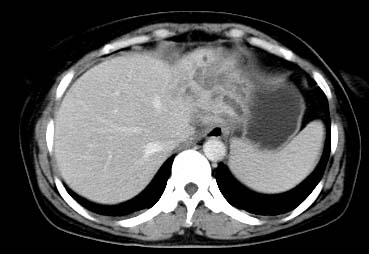

以下是引用西北一只狼在2008-6-30 20:58:00的发言:[br]肝左叶胆管细胞ca并肝门淋巴结转移、胰腺、胃小弯浸润

以下是引用ydx_74在2008-6-30 21:54:00的发言:[br]左叶胆管细胞ca并肝门淋巴结转移、胰腺、胃小弯浸润